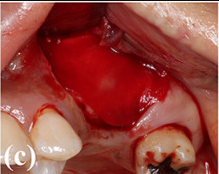

Process diagram of clinical procedure; a) Cracked tooth #25; b) #25 Atraumatic extraction; c) Placement of HA hydroxyapatite granules in alveolar socket after atraumatic extraction, with closing of the socket by Cytoplast™ and suturing; d, e) After four months, harvesting of the grafted area with a trephine bur in formalin solution.

Case photos provided by: Customized three-dimensional printed ceramic bone grafts for osseous defects: a prospective randomized study.

Clinical photographs of the surgery. (a) A bony access window was created on the lateral wall of the maxillary sinus. (b) 3DPHA‐PCL was filled in the sinus after detaching the sinus membrane. (c) A collagen membrane was applied to cover the access window. (d) Dental implants were placed on #15 and #16 areas. (e) A bone core biopsy was performed during drilling. (f) The obtained specimen. (g) An implant prosthesis was delivered (#17 was extracted).